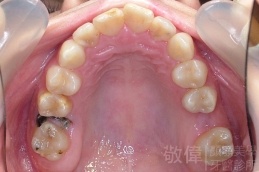

變臉矯正,原來戽斗妹跟大歪臉變成自信正妹

經由本院3D數影X光影像儀分析、與3D齒顎顏矯正技術,再配合口腔顎面正顎專科醫師施以正顎手術治療,雙方共同合作,使患者臉部外觀有很好的改善,大歪變小歪,產生了天南地北的大改變,她的人生也整個變得不一樣。

因為矯正與正顎手術的配合,使「戽斗妹」變成了「陽光正妹」,完全的改變了她的人生,在面對各種場合、與人交際都散發出自信微笑。所以,奉勸家長,如果小朋友有臉顎畸型的問題,應該考慮配合做這種簡單、安全、有效的正顎手術。